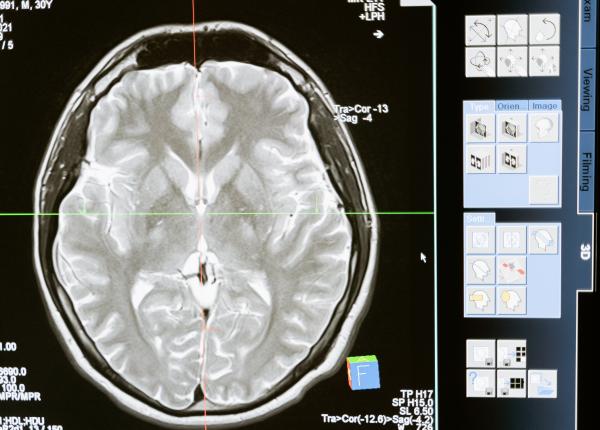

Biopsie și examen anatomopatologic sunt două tipuri de analize ale țesuturilor. Medicii explică diferența între cele două.